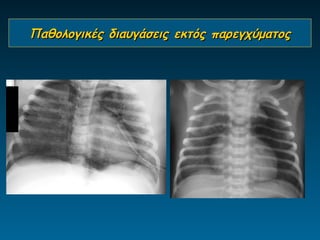

Παθολογικές διαυγάσεις εκτός παρεγχύματος

Διαφυγές αέρα

4 ετών λαρυγγο-τραχειο-βρογχίτιδα